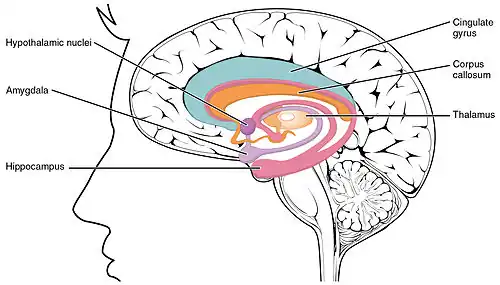

LENAS is seen with damage to the white matter and axons within the brain. The external human LENAS brain shows findings in several major structures. There is mild atrophy of the frontoparietal regions of the brain and a mild reduction of the thalamus and rostral (front) part of the caudate nucleus (which is located in an area of the brain called the basal ganglia).[5] Abnormalities in the frontal, frontoparietal, and temporal lobes are most severe and predominant with LENAS and asymmetry of the cerebral hemispheres has sometimes been found.[5] LENAS also may show moderately enlarged lateral ventricles and atrophy in corticospinal tracts as well as in the pons.[5]

The area where it is seen to be the most pronounced abnormalities appear in the white matter below the pre- and postcentral gyri that extend through the posterior limb of the internal capsule into pyramidal tracts of the brain stem.[5]

- The corpus callosum is variably affected.

- Reactive astrocytes and macrophages are present, but no inflammation appears.

- The cerebral cortex and basal ganglia are normal and contain no or only few spheroids.

- Within the cerebellum, there is a marked loss of Purkinje cells seen but cerebral white matter is normal.